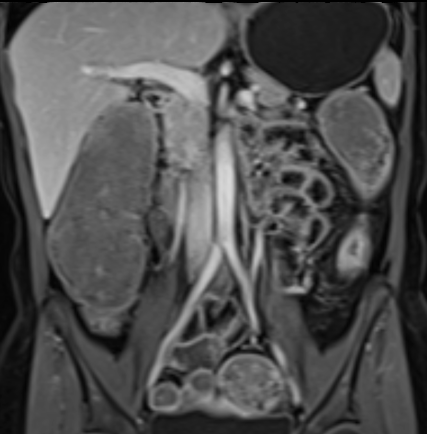

Bệnh nhân nữ 48 tuổi, đang điều trị bằng thuốc kháng TNF, được chỉ định nội soi đại tràng.

Phát hiện hẹp lòng ruột ở đại tràng sigma, không thể vượt qua được khi nội soi.

MR-enterography được thực hiện để đánh giá mức độ lan rộng của chỗ hẹp.

Ruột non bình thường, nhưng ghi nhận các đoạn hẹp ở đại tràng xuống và đại tràng ngang.

Cả hai đoạn hẹp đều có thành ruột dày đến 8 mm và ngấm thuốc rõ rệt theo kiểu niêm mạc ở đại tràng xuống và kiểu phân lớp ở đại tràng ngang.

Giãn ruột trước chỗ hẹp được ghi nhận ở cả hai đoạn.

Do các chỗ hẹp này không hiện diện khi nội soi đại tràng trước khi điều trị kháng TNF, nhiều khả năng chúng đã hình thành trong quá trình điều trị.

Do đó, quyết định phẫu thuật cắt đại tràng gần toàn bộ với miệng nối hồi-sigma đã được đưa ra.